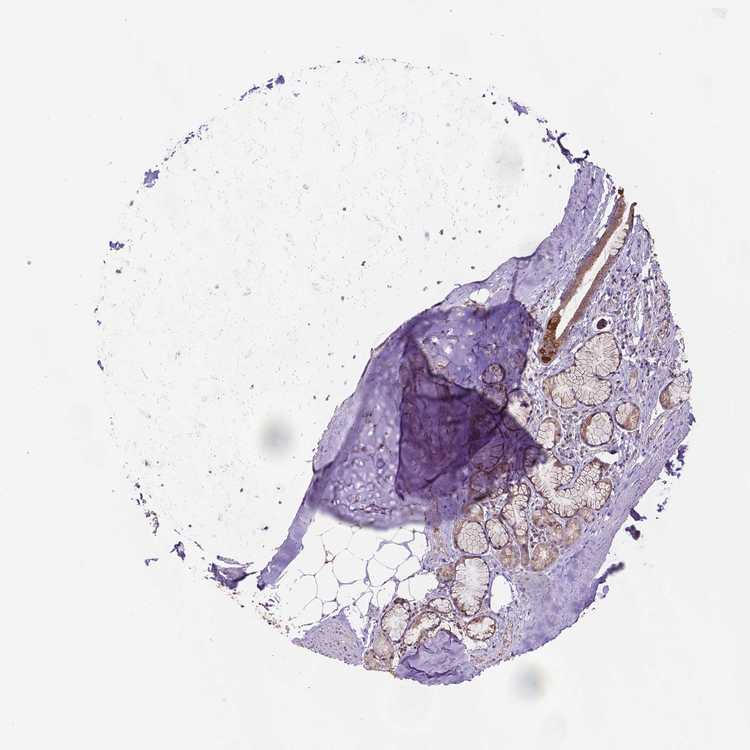

ADIPOSE TISSUE - Antibody stainingi

Antibody staining in the annotated cell types in the current human tissue is reported as not detected, low, medium, or high, based on conventional immunohistochemistry profiling in selected tissues. This score is based on the combination of the staining intensity and fraction of stained cells.

Each image is clickable and will lead to virtual microscopy that enables deeper exploration of all samples and also displays staining intensity scores, fraction scores and subcellular localization as well as patient and tissue information for each sample.

Antibody HPA063324

Adipocytes Not detected